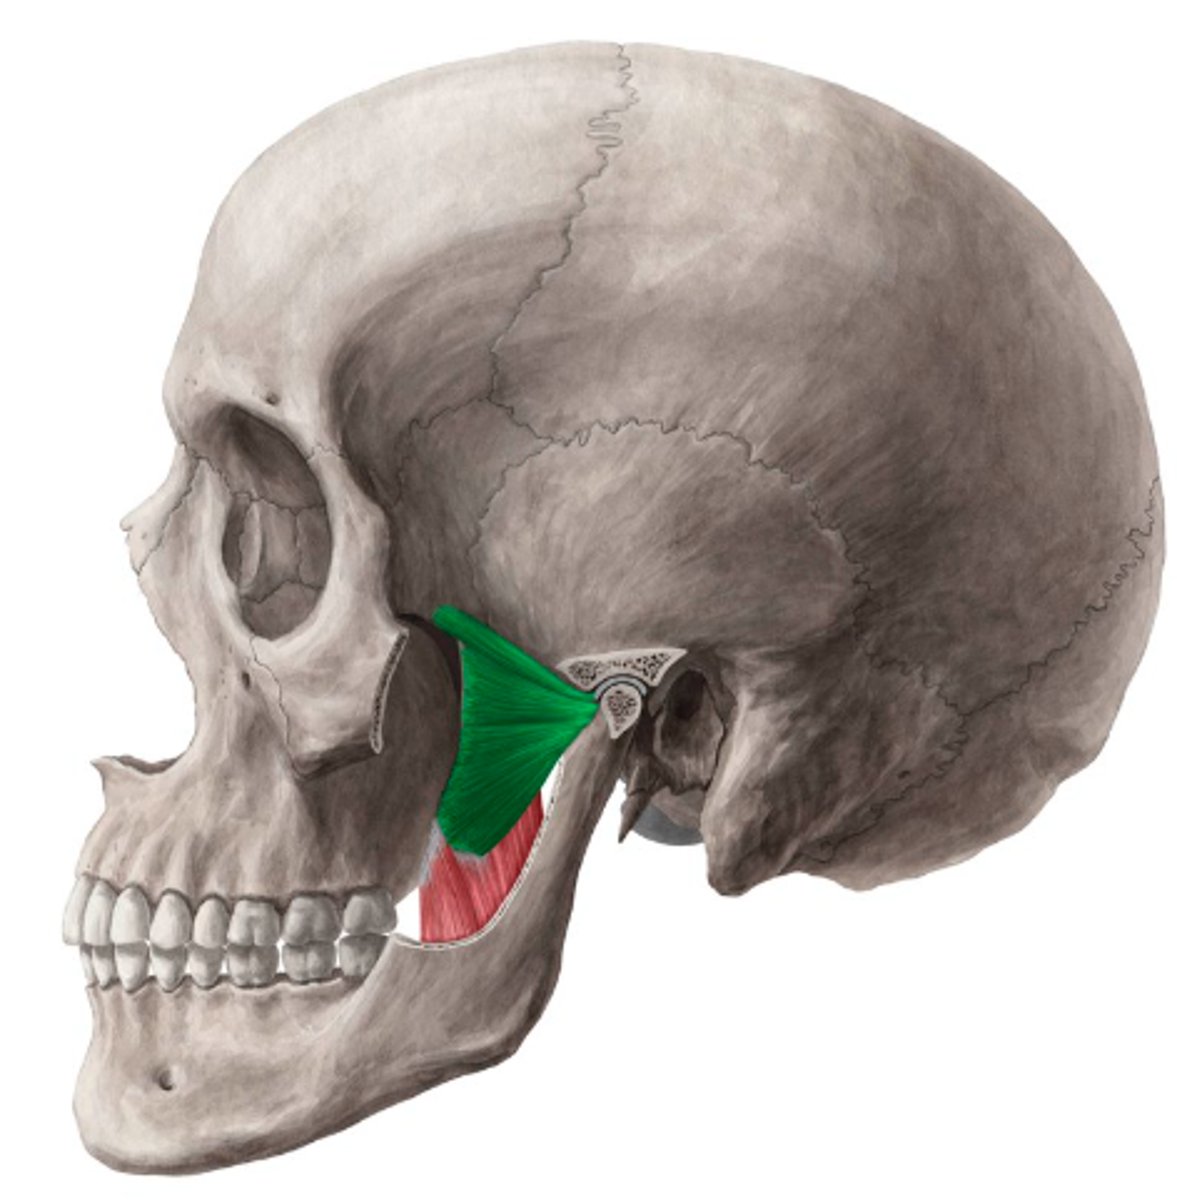

deep masseter

superficial masseter

temporalis

lateral pterygoid

lateral pterygoid, superior part

lateral pterygoid, inferior part